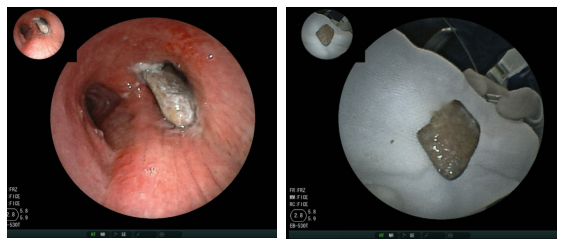

9个月的宝宝反复肺炎3个月,ct提示支气管异物纤维支气管镜下见异物

支气管镜检查:双肺支气管各段粘膜充血,肿胀,可见纵行皱褶,支气管灌